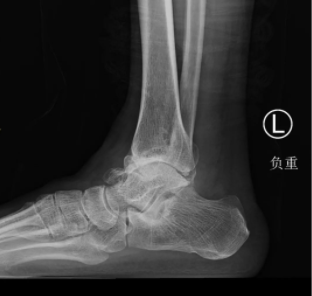

本次接受全踝关节置换术治疗的是一名60岁的男性患者,该患者8年前扭伤左踝,予保守治疗,后出现左踝关节反复疼痛。3个月前疼痛加重、无法行走,于是来我院足踝外科就诊。

术前X光片

必威官方首页官网betway足踝外科石荣剑主任医师和曹广超主任带领团队经过反复考量,为患者及其家属提供了关节融合、关节置换两种治疗方案。为最大程度地改善踝关节功能,提升生活质量,患者及家属最终决定选择进行既能消除疼痛,又能保留踝关节活动度的人工全踝关节置换术。

经过周密的术前准备,1月18日,石荣剑主任医师、曹广超副主任医师和李亮主治医师手术团队为患者进行了左踝人工全踝关节置换手术,手术顺利。术中见关节歪向内侧,骨赘增生严重,首先松解挛缩的韧带,使用提前精准设计打印的3D导板,透视调整力线,截骨安装适合型号的关节假体,最后调整内外侧软组织平衡,增加关节稳定性。